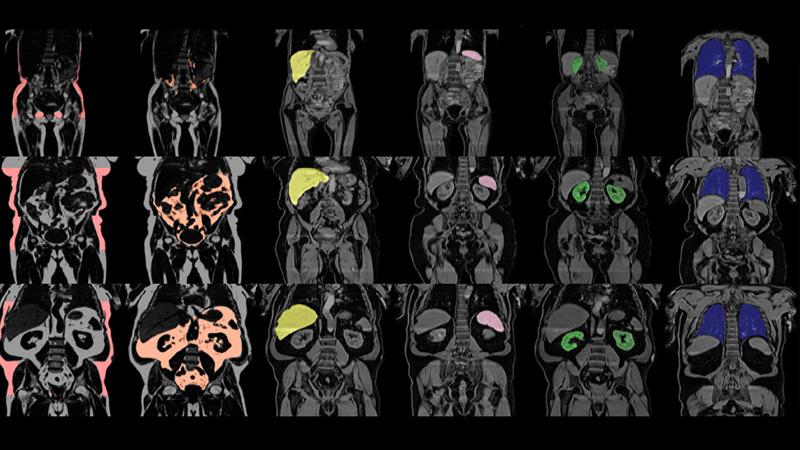

The study, recently published in the renowned scientific journal eLife, includes image-based measurements of organ volumes including the liver, pancreas, kidneys, spleen, lungs and adipose tissue depots, as well as fat and iron content of the liver and pancreas. The researchers have combined these measurements with the numerous markers of lifestyle and health also available in the UK Biobank to help understand the role of organ volume and composition in health and disease.